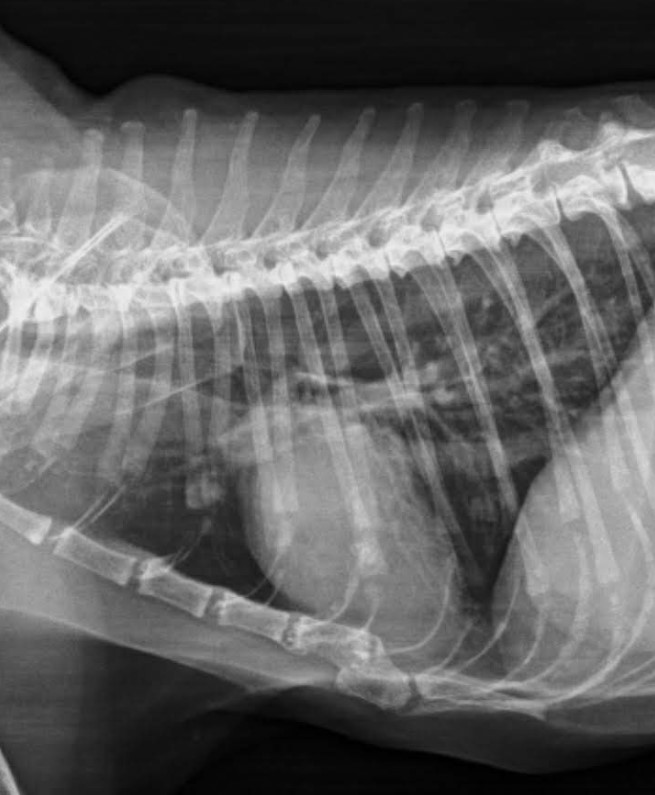

Negrita, diagnosed with Lung Cancer and Cardiomegaly

After being misdiagnosed with Feline Asthma back in August 2022 and not showing signs of improvement upon treatment, we took Negrita for a second opinion in September 2022; she was then diagnosed with early-stage Lung Cancer.

At the beginning of 2023, she went for a checkup with another vet who re-evaluated her condition; new tests and X-rays revealed she also suffers from Cardiomegaly.

Last Wednesday, Negrita went for yet another vet check up as her condition was gradually deteriorating. She was very stressed so she had to be sedated to be able to run the tests. New X-rays revealed an enlargement of her heart (Cardiomegaly).

After a closer look at Negrita’s X-rays the vet confirmed she has a few lung tumors that will eventually grow and spread and so there is not much more we can do for her at this point but to provide love and comfort until the time comes to let her go.

She had been misdiagnosed with a pulmonary infection and new tests (X-rays) were needed to re-evaluate her condition to finally diagnose her with Feline Asthma which was to be treated with corticosteroid shots every 2 weeks to reduce inflammation in the lungs.